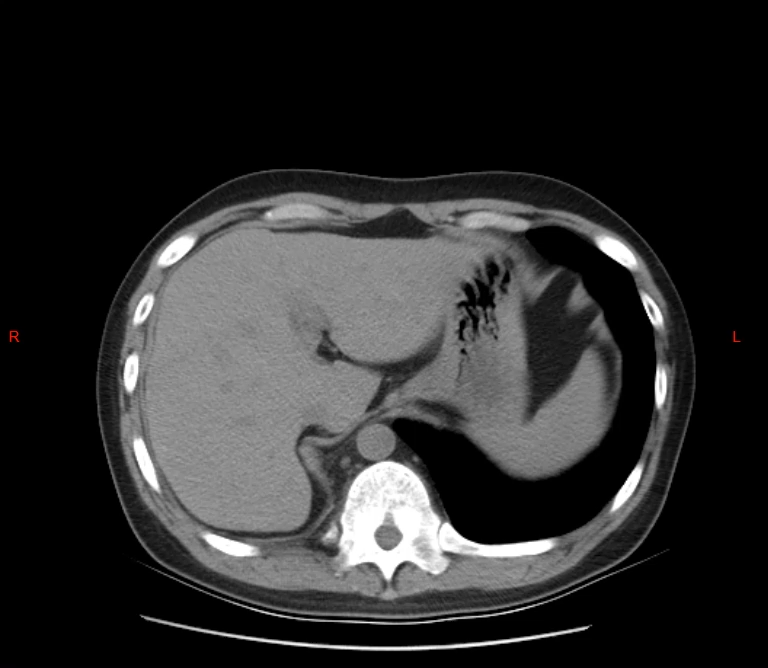

2020年术后复查

2020年术后复查